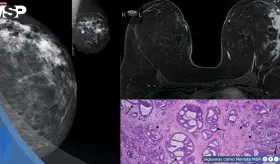

La paciente desarrolló simultáneamente un carcinoma mamario triple negativo de rápido crecimiento y un adenocarcinoma rectal invasivo, ambos confirmados como tumores primarios independientes.

A pesar de mostrar un aumento radiológico del tumor durante la quimioinmunoterapia neoadyuvante, la cirugía reveló una respuesta patológica completa, subrayando la complejidad de la pseudoprogresión.

Este caso destaca la importancia de los estudios de imagen multimodales y plantea la necesidad de reconsiderar las estrategias de detección en mujeres no fumadoras, población en la que se observa un incremento creciente de esta neoplasia.